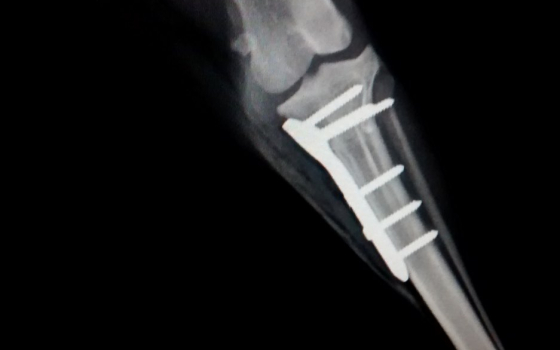

A Ruptura de ligamento cruzado cranial (RLCcr) é uma afecção muito comum nos cães, este caso refere-se a um cão macho mancando de forma aguda que ao exame foi feito o diagnostico de RLCcr. Optou-...